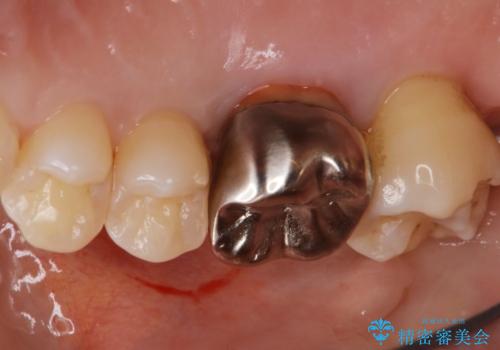

- 右上4、5の歯がしみるのを治したいという主訴で来院されました。精査の結果隣接面う蝕と診断し、適合がよく見ためも良いセラミックインレーでの治療を行いました。

セラミックインレーを入れた後は歯がしみることはなくなり、白く丈夫な被せ物が入り満足いただけました。